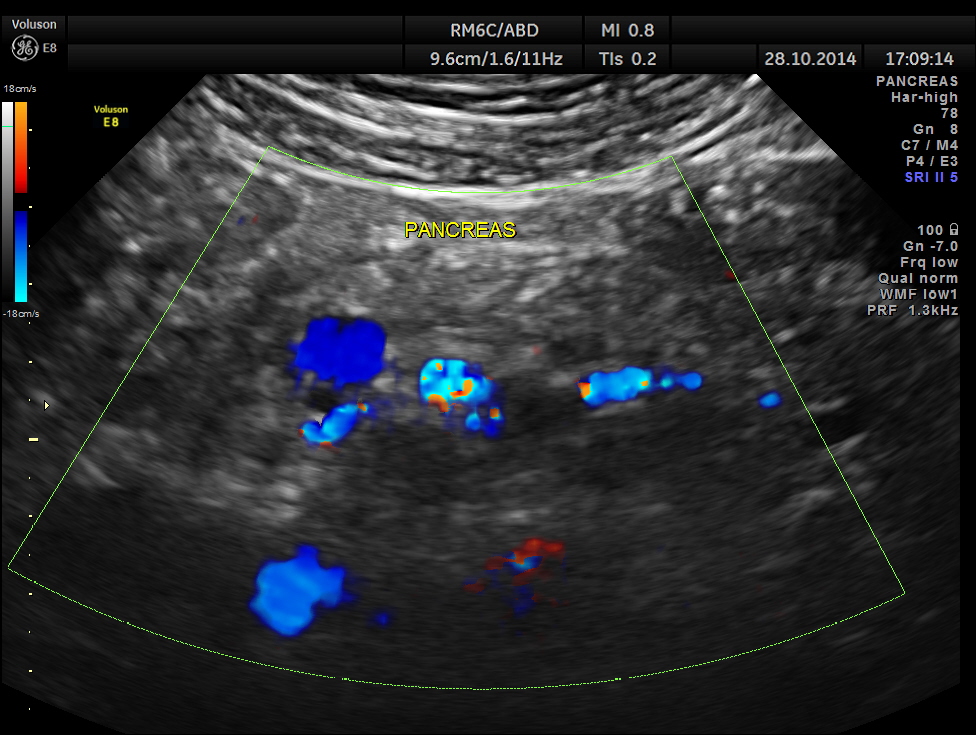

STIC HD flow image.

Main portal vein show flow reversal ( blue colour ) – centri-fugal flow suggestive of portal hypertension.

Epigastric varices are also seen.